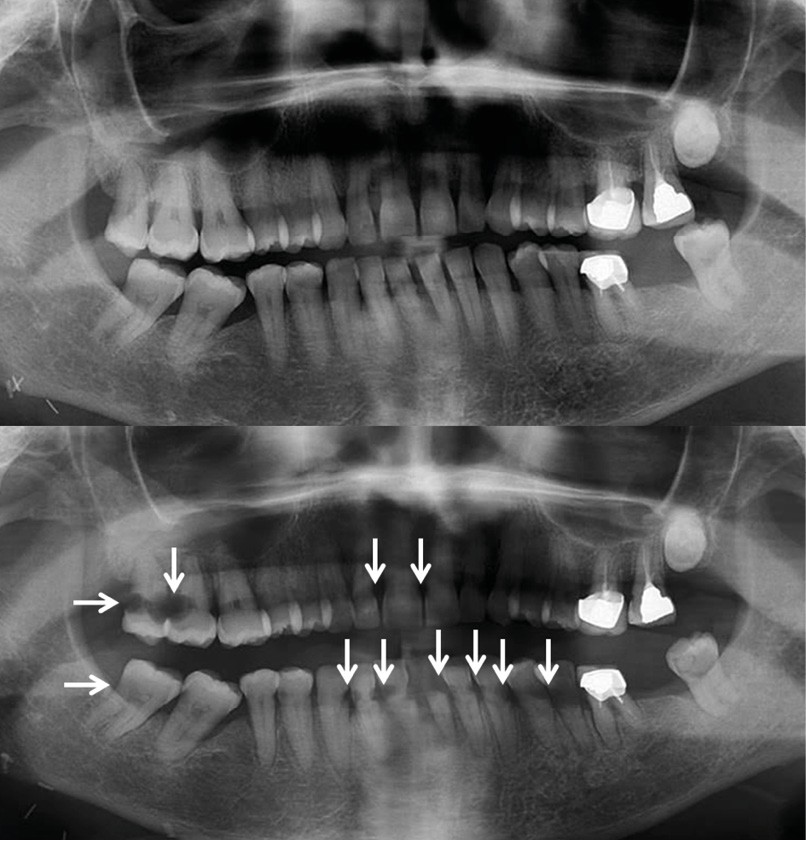

La probabilité et la gravité de ces effets indésirables dépendent d’un certain nombre de facteurs, comme la dose totale de radiations administrées, la durée de l’irradiation, et les parties de la tête et du cou concernées. Au niveau de la cavité buccale, les toxicités associées à la radiothérapie incluent l’altération du renouvellement des muqueuses de la cavité buccale, la modification de la production et de la qualité de la salive, provoquant une hyposialie ou asialie, une modification de la flore buccale et une altération du goût (fig. 1 et 2). Tous ces effets indésirables jouent un rôle fondamental dans la dégradation de l’état bucco-dentaire et ont des impacts directs sur de la qualité de vie du patient [3-5].